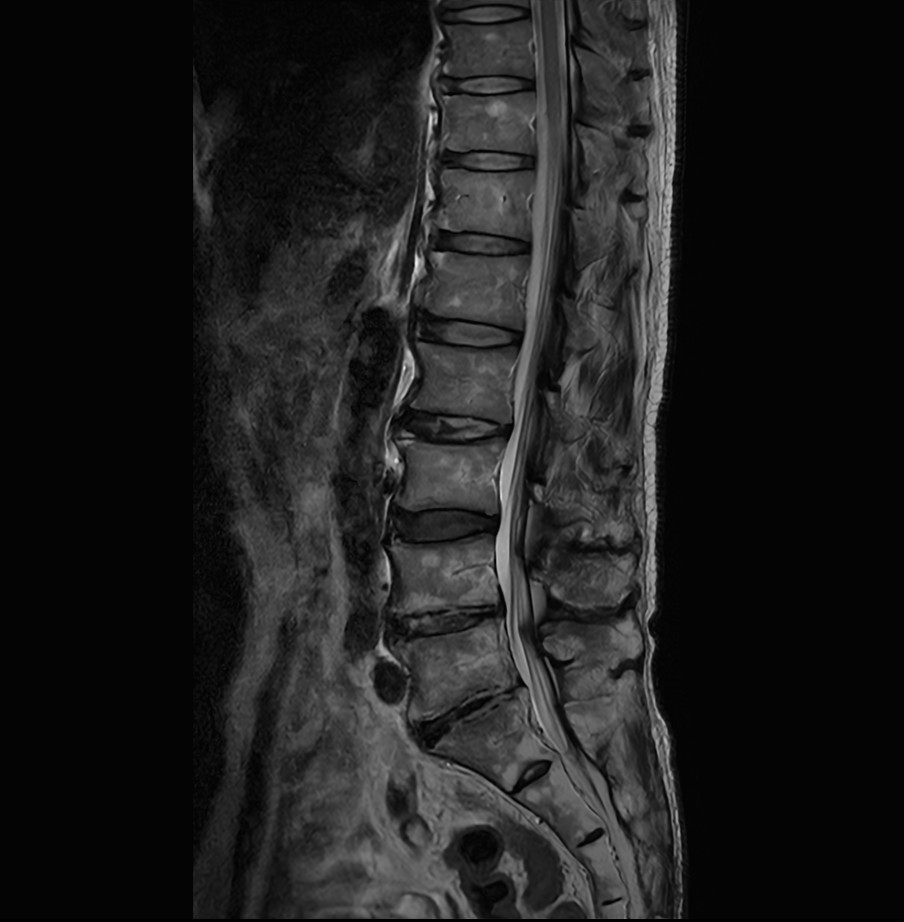

Sagittal T2w TSE